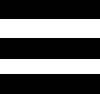

Luxus Torso Modell, mit weiblichen & männlichen Geschlechtsorganen, 24-teilig

Luxus Torso Modell, mit weiblichen & männlichen Geschlechtsorganen, 24-teilig – 3B Smart Anatomy

Der 3B Scientific Luxus-Torso bietet Ihnen alle Möglichkeiten für ausführliche Demonstrationen. Sie erhalten hunterprozentige Qualität und einen hohen Grad an Detailarbeit. Die Beschaffenheit der erweiterten Torso-Version ist beeindruckend, genau wie sein Preis! Beantworten Sie mit seiner Hilfe alle Fragen zur inneren Anatomie des Menschen. Er ist zerlegbar in:

– 3-teiligem Kopf

– 2-teiligem Magen

– 4-teiligem Darmpaket

– Weibliche Brustdecke (2-teilig)

– 2 Lungenhälften

– 2-teiliges Herz

– Leber mit Gallenblase

– Vordere Nierenhälfte

– 3-teiliger weiblicher Genitaleinsatz mit Embryo

– 4-teiliger männlicher Genitaleinsatz

Alle Organe in diesem menschlichen Torso sind von Hand bemalt.